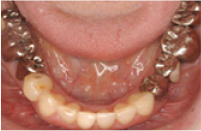

治療前

治療後